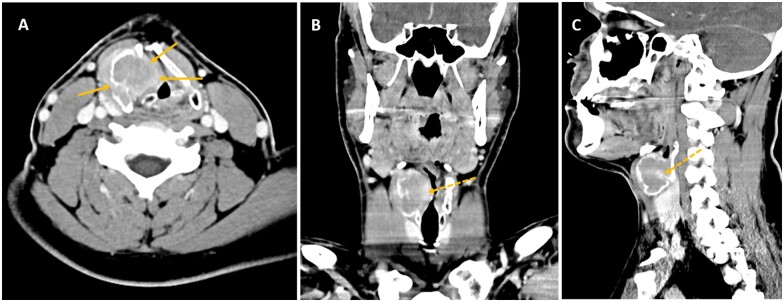

喉巨细胞瘤(GCT)极为罕见。受影响最大的结构是甲状软骨,文献中仅报道了 44 个病例。1 在临床上,它们的首发症状通常是可触及的颈部肿块,根据肿块的大小和位置,通常伴有声音嘶哑、呼吸困难和/或吞咽困难。GCT 属于良性肿瘤,但由于其侵袭性局部表现可导致气道阻塞,并可模拟恶性肿瘤,因此对这种实体的认识至关重要。鉴别诊断的范围很广,仍然是临床和放射学上的难题。事实上,最终诊断要通过术后组织学检查来确定。手术是首选的治疗方法,但可能会影响嗓音质量。对于手术切除不彻底和手术风险较高的病变,地诺单抗治疗是一种有价值的选择。我们将与大家分享我们对一名表现为声门上肿块的年轻成人 GCT 的治疗经验。

Giant cell tumours (GCTs) of the larynx are extremely rare. The most affected structure is the thyroid cartilage and only 44 cases are reported in the literature.1 Clinically, their first manifestation is usually a palpable neck mass, often accompanied by hoarseness, dyspnoea, and/or dysphagia depending on size and location. GCTs are benign neoplasms, yet awareness of this entity is crucial as their aggressive local behaviour can cause significant morbidity with airway obstruction and can simulate a malignancy. The differential diagnosis is broad and remains a clinical and radiological challenge. Indeed, the final diagnosis is established by histology postoperatively. Surgery is the preferred treatment but may impair voice quality. For incomplete surgical resections and high surgical risk lesions, denosumab treatment is a valuable option. We share our experience on GCTs in a young adult presenting as a supraglottic mass.